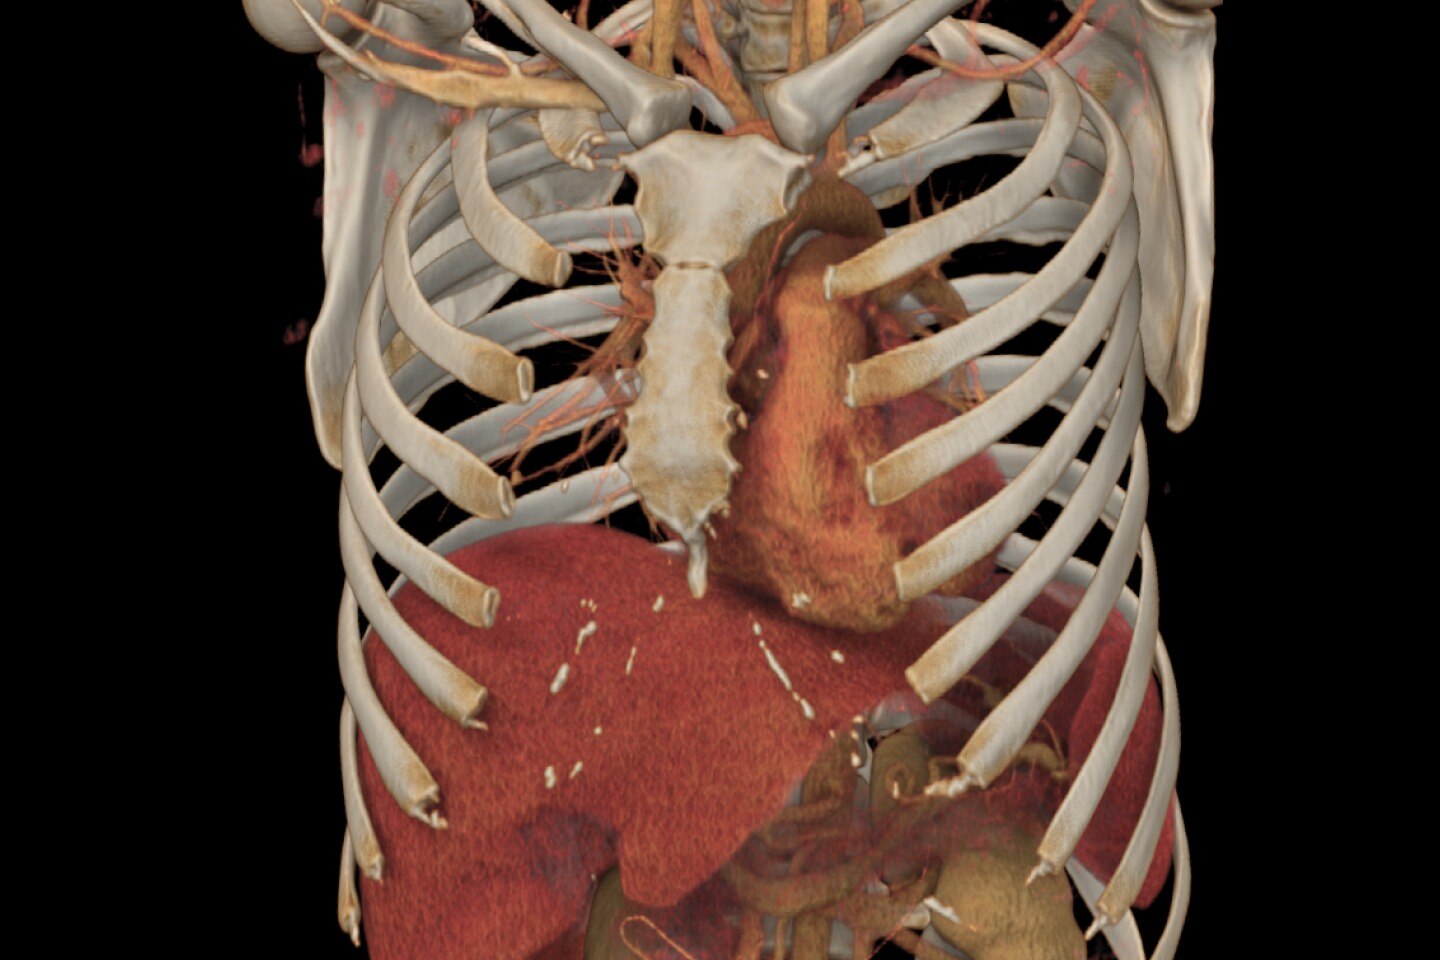

Mayor adaptabilidad con un túnel del estativo de 70 cm y un diseño optimizado de la mesa

Con un túnel más grande y una capacidad de carga de paciente de hasta 180 kg (396 lb), Revolution Aspire le ayuda a adquirir imágenes con facilidad de una gran variedad de pacientes hospitalizados, desde ancianos hasta pacientes pediátricos y pacientes de mayor tamaño.

Diagnóstico más fundamentado con mayor inteligencia de imágenes mediante Smart MAR

Smart MAR se ha diseñado para mostrar detalles anatómicos que se ven oscurecidos a causa de los artefactos metálicos, de modo que los profesionales de la salud pueden usar exploraciones de TC, diagnosticar enfermedades y definir objetivos y órganos críticos con mayor confianza.